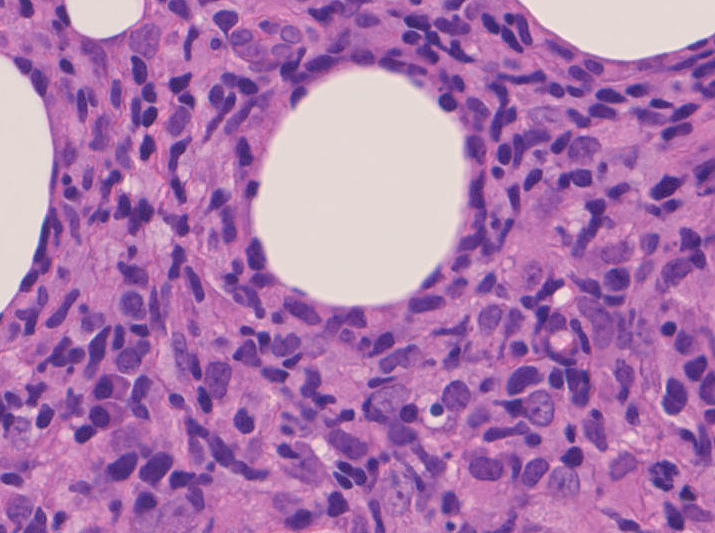

組織所見*16*17*18

皮下組織に優位な, 小~中型 Tリンパ球の密な浸潤が特徴。ときに大型リンパ球や組織球が混在する。 リンパ球の異型は, わずかなものから明瞭な異型を示す症例までさまざまである。